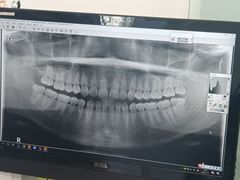

• 马泷齿科·皓康门诊(尚都SOHO店)

• -马泷齿科·皓康门诊(尚都SOHO店)

MATH | 22-01-20